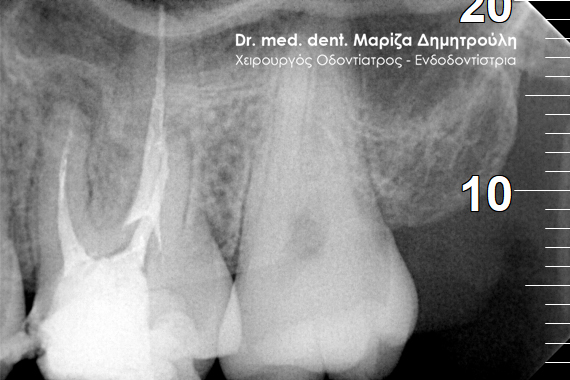

Περιστατικό – Επανάληψη απονεύρωσης και προσθετικής

Η ασθενής παρουσιάστηκε στο ιατρείο με την επιθυμία να ξανακολληθούν οι στεφάνες της στους δυο κάτω αριστερούς προγομφίους, γιατί τον τελευταίο καιρό της αισθανόταν “λίγο χαλαρές”.

Η κλινική εξέταση των δοντιών έδειξε κάτι πιο πολύπλοκο απ΄ αυτό που περιέγραφε η ασθενής. Οι στεφάνες ήταν πράγματι χαλαρές και δεν προσάρμοζαν πάνω στα δόντια, γιατί τα δόντια κάτω από τις στεφάνες είχαν επανατερηδονιστεί.

Η ακτινογραφική εξέταση αποκάλυψε ότι και τα δύο δόντια είχαν απονευρωθεί στο παρελθόν, έφεραν το καθένα στο εσωτερικό χυτό μεταλλικό άξονα και στο ακρορρίζιο διαπιστώθηκε μια περιακρορριζική αλλοίωση. Η αλλοίωση αυτή μαρτυρά τη φλεγμονή του δοντιού στο άκρο της ρίζας.

Μετά από συνεννόηση με την ασθενή αποφασίστηκε το παρακάτω σχέδιο θεραπείας:

1. Αφαίρεση των παλιών στεφανών (θηκών δοντιού)

2. Αφαίρεση του χυτού μεταλλικού άξονα από το εσωτερικό του ριζικού σωλήνα

3. Επανάληψη της απονεύρωσης

Αφού ολοκληρώθηκαν οι παραπάνω εργασίες πραγματοποιήθηκε αποκατάσταση των δοντιών με άξονες υαλονημάτων και κατασκεύη καινούριων στεφανών. Οπώς φαίνεται και στην τελική ακτινογραφία 6 μήνες μετά την διεκπεραίωση του σχεδίου θεραπείας η φλεγμονή στο ακρορρίζιο του δοντιού είχε ήδη υποχωρήσει.

ΠΡΙΝ

Έλεγχος αφαίρεσης άξονα και παλιάς απονεύρωσης

Τελική ακτινογραφία